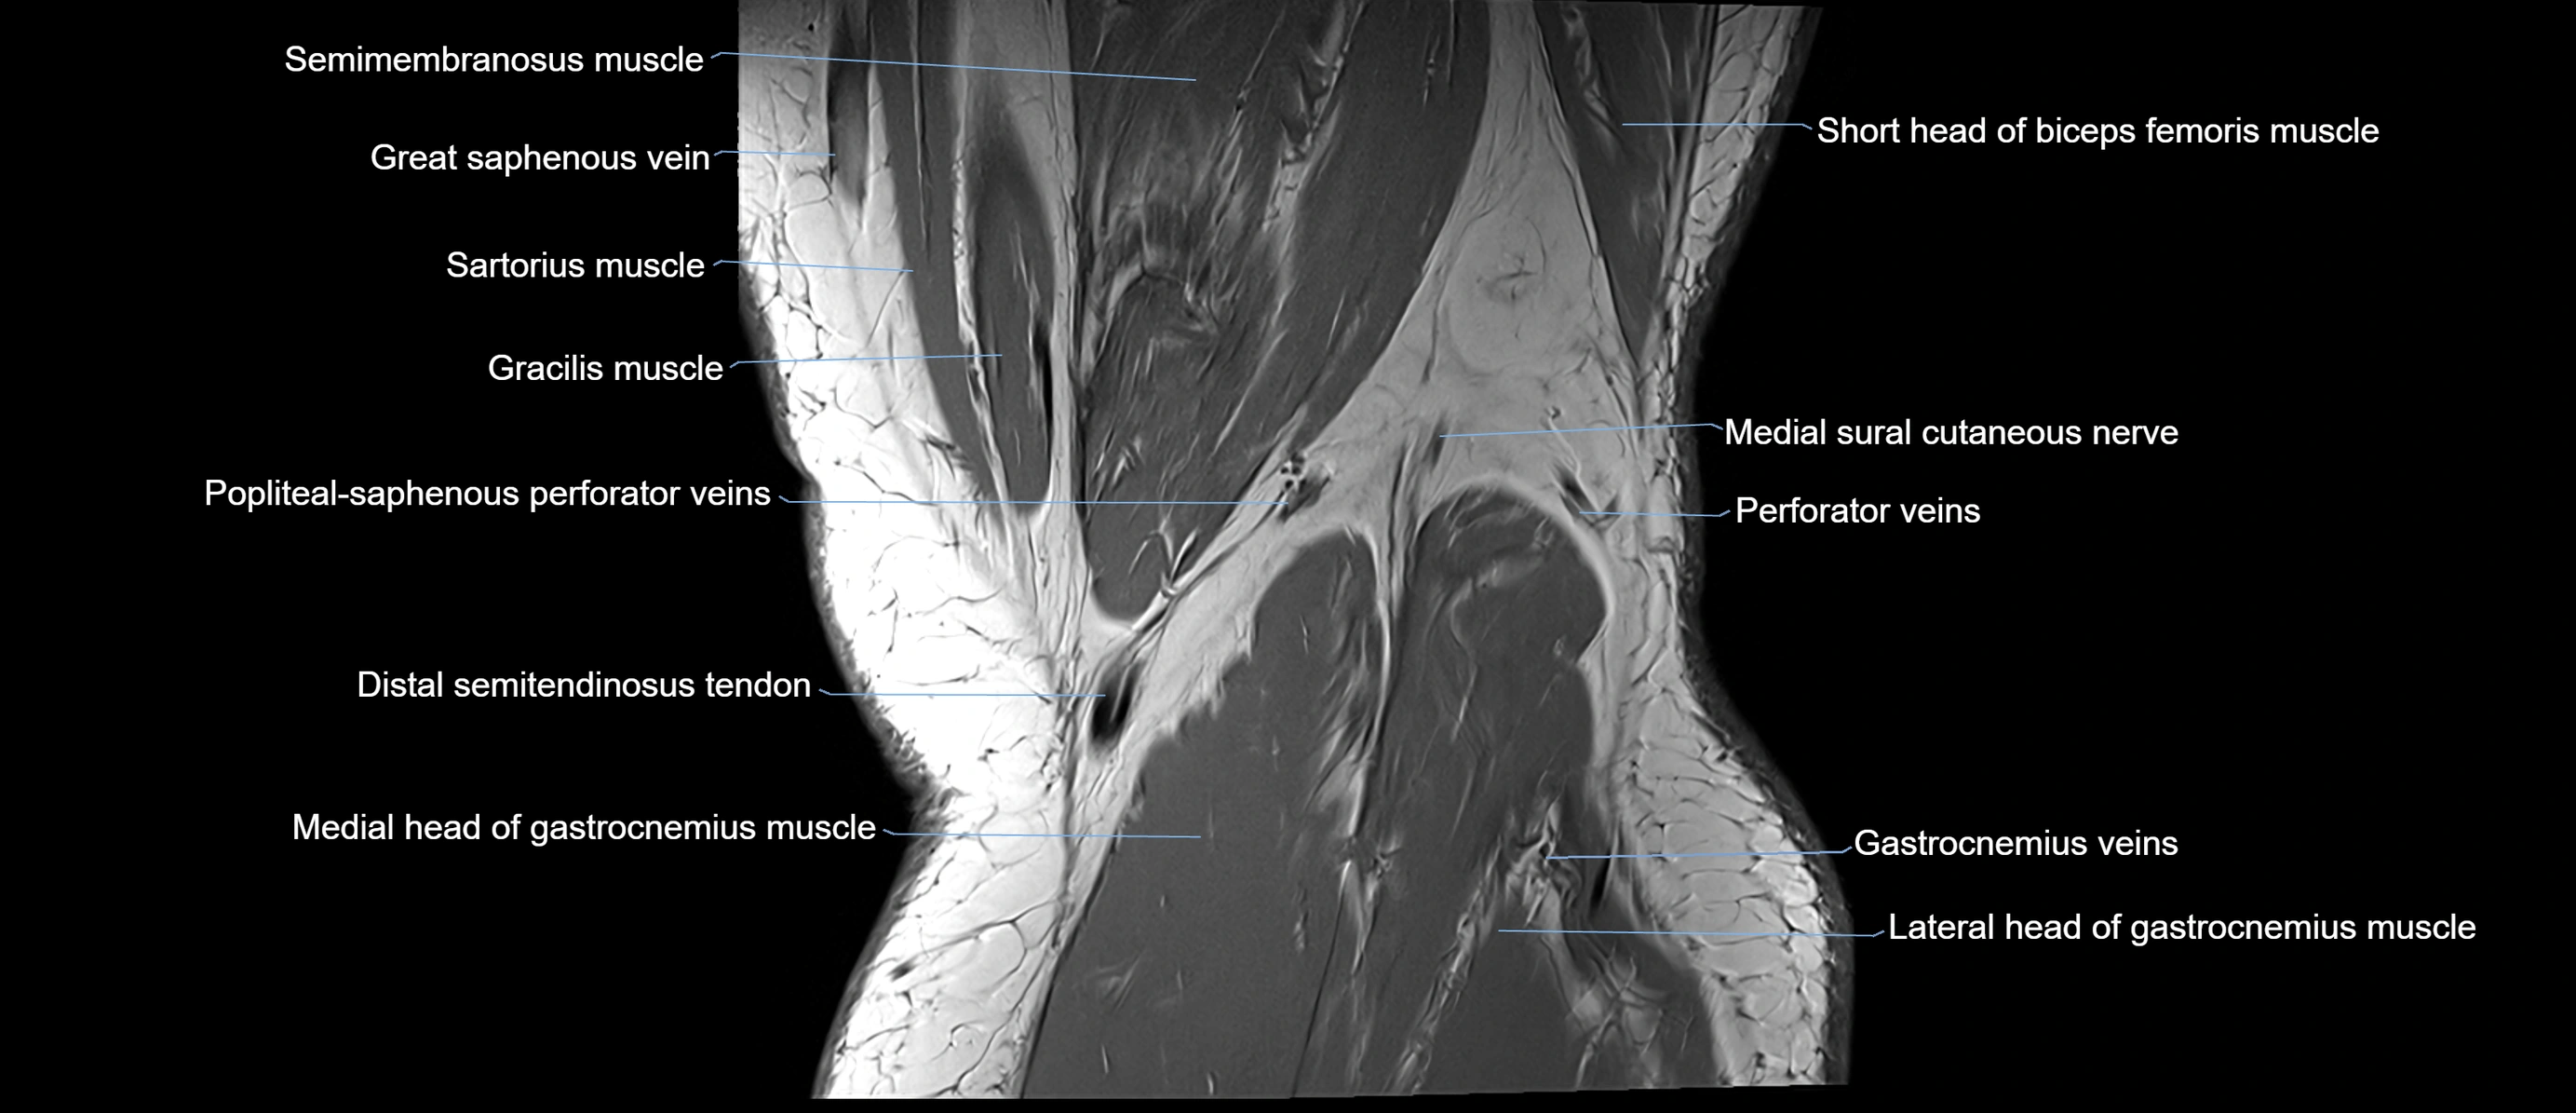

- Semimembranosus muscle

- Sartorius muscle

- Gastrocnemius muscle

- Medial head of gastrocnemius muscle

- Lateral head of gastrocnemius muscle

- Medial sural cutaneous nerve

- Popliteal–Saphenous perforating veins

- Distal semimembranosus tendon

- Distal semitendinosus tendon

- Small saphenous vein

- great saphenous vein